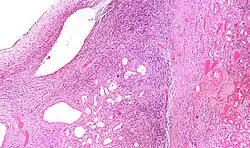

Micrograph of a cystic nephroma (left of image). Normal kidney is seen on the right. H&E stain.

A cystic nephroma, also known as multilocular cystic nephroma, mixed epithelial stromal tumour (MEST) and renal epithelial stromal tumour (REST),[1] is a type of rare benign kidney tumour.